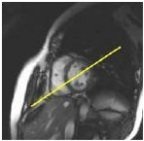

1. From the short axis view, prescribe (yellow line indicates graphic location) and acquire a 4-chamber view.

Figure 1. Prescribe 4-chamber view